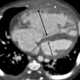

Pulmonary venous hypertension

Pulmonary hypertension (PH or PHTN) is a condition of increased blood pressure within the arteries of the lungs. Symptoms include shortness of breath, syncope, tiredness, chest pain, swelling of the legs, and a fast heartbeat. [Source: Wikipedia ]